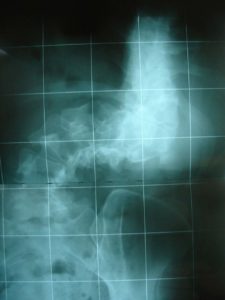

Εικόνα 2

Μετωπιαία ακτινογραφία Σπονδυλικής Στήλης σε όρθια στάση. Ο πάσχων, 9 χρονών, φορά υπομασχάλιο κηδεμόνα.

Σύμφωνα με τις δοθείσες πληροφορίες υπό του ιδίου και του αμέσου περιβάλλοντος, το παιδί φορούσε τον κηδεμόνα για μερικές ώρες την ημέρα ο οποίος σημειωτέον δεν είχε ουσιαστική εφαρμογή στο σώμα του. Μετά από μερικά χρόνια στην ηλικία των 15 χρονών ο κηδεμόνας εγκαταλείφθηκε.